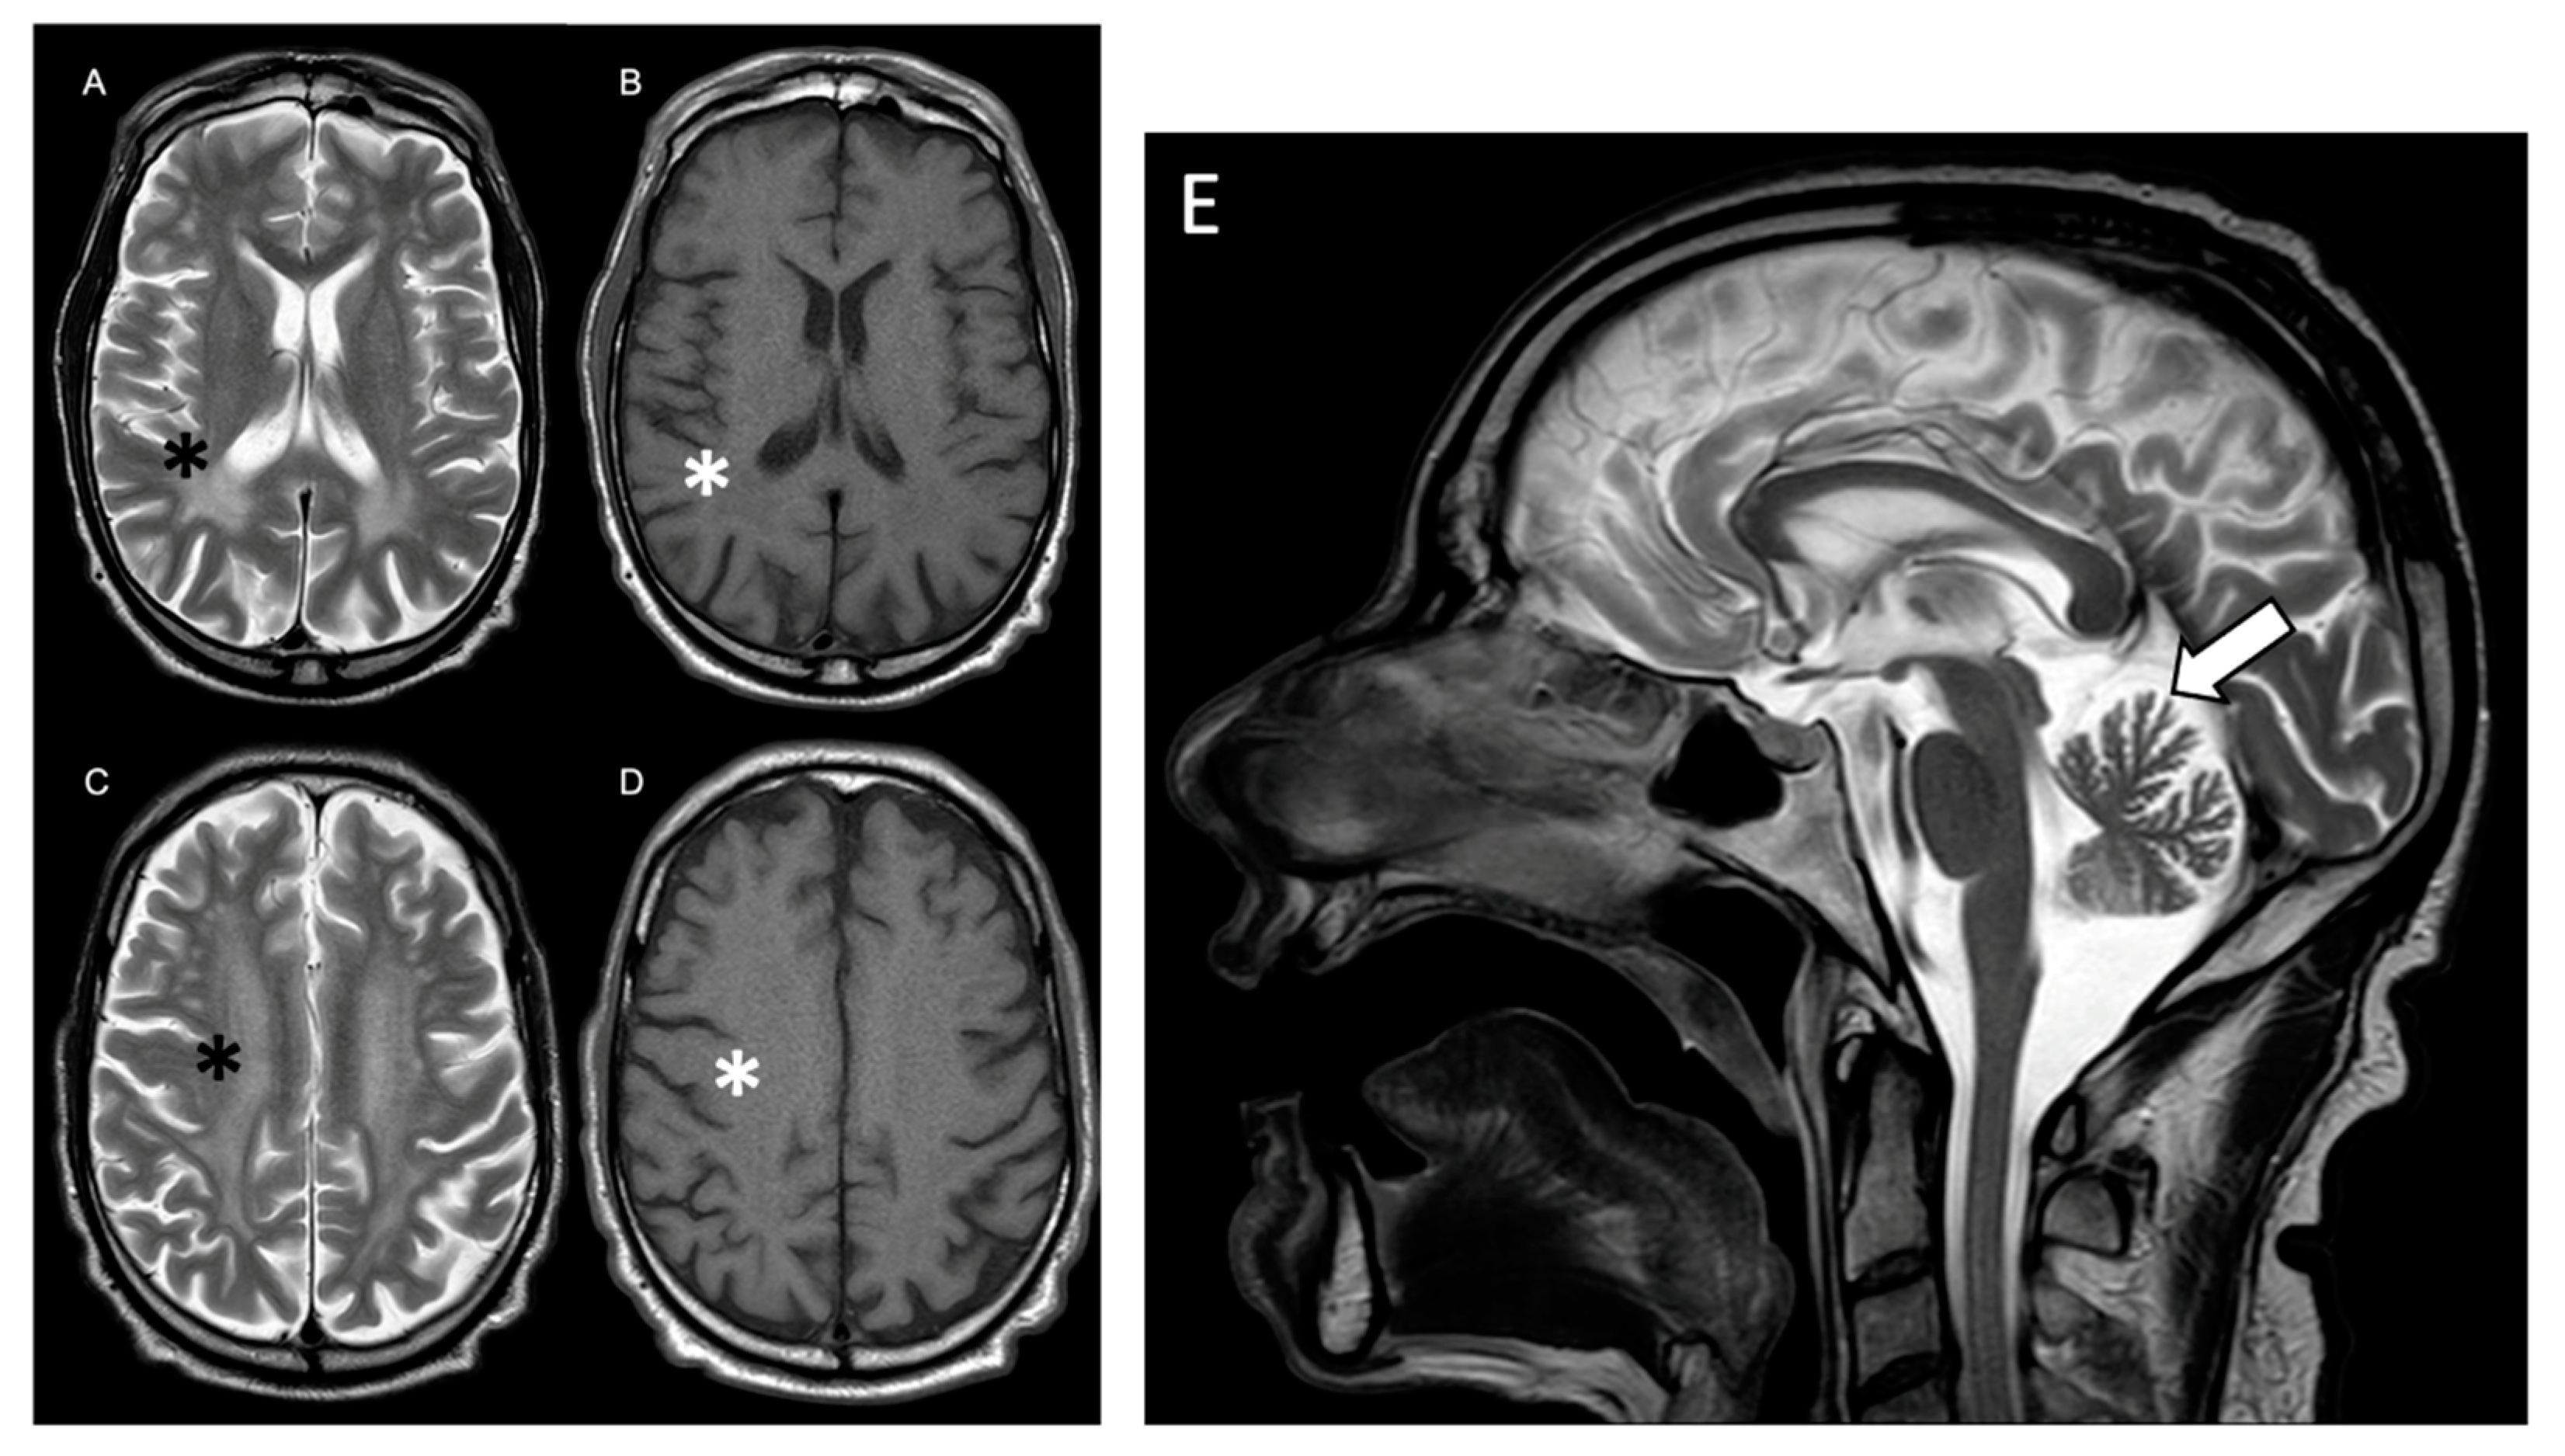

Pasquetti, D.; Gazzellone, A.; Rossi, S.; Orteschi, D.; L’Erario, F.F.; Concolino, P.; Minucci, A.; Dionisi-Vici, C.; Genuardi, M.; Silvestri, G.; et al. Triple Genetic Diagnosis in a Patient with Late-Onset Leukodystrophy and Mild Intellectual Disability. Int. J. Mol. Sci. 2024, 25, 495. https://doi.org/10.3390/ijms25010495